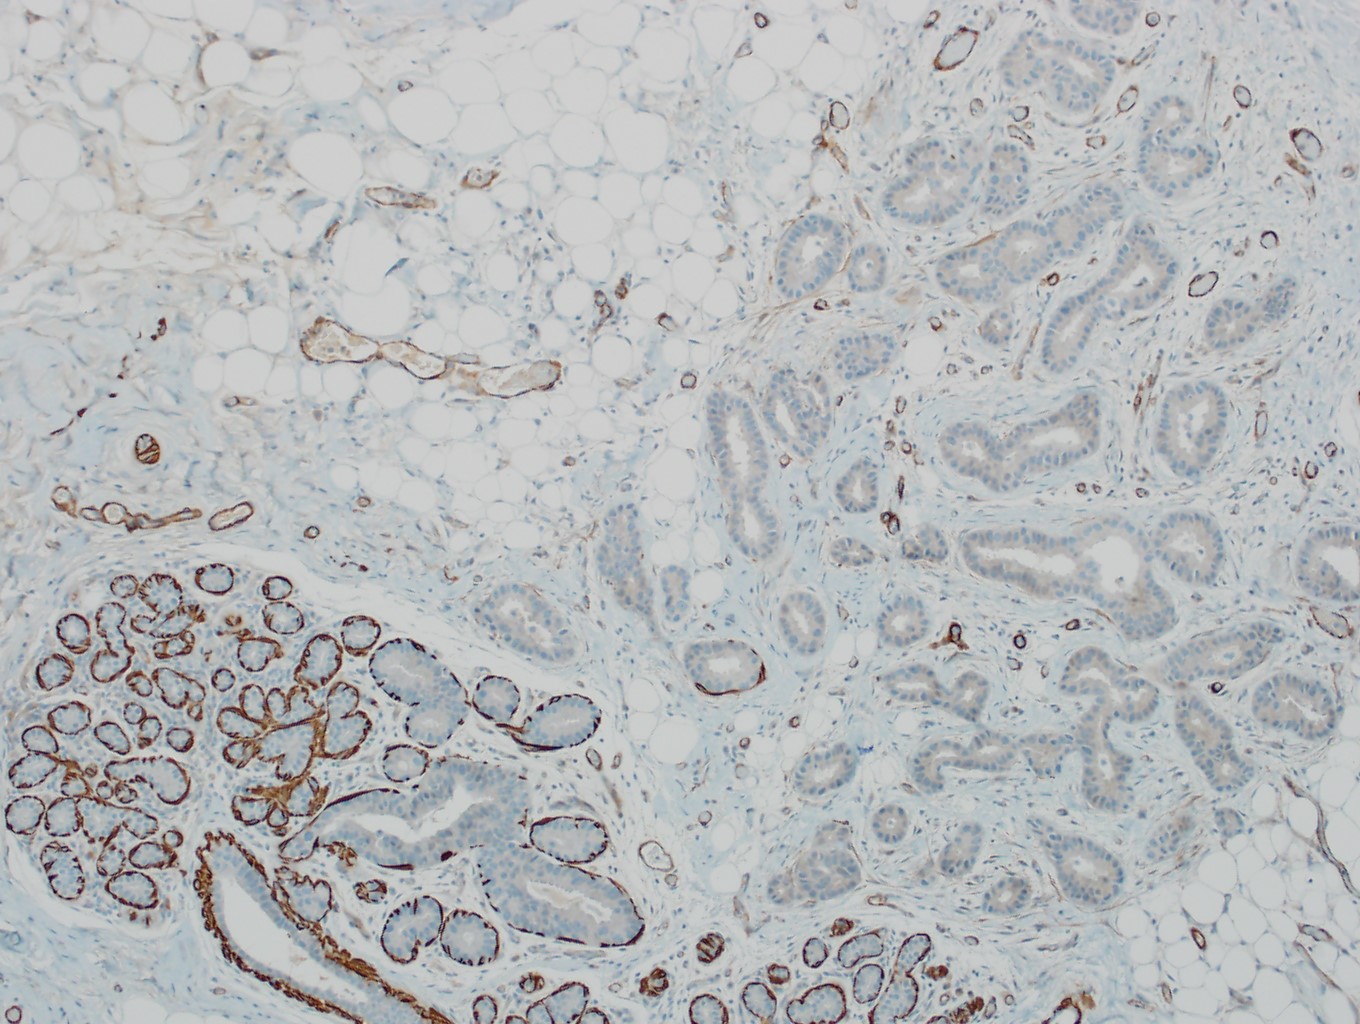

- No myoepithelial cell lining (as seen in DCIS or benign lesions)

- Angiolymphatic invasion in 35%; differs from tissue retraction because:

- Occurs outside margin of carcinoma

- Does not conform precisely to space it is in

- Endothelial lining is present and is CD31+, ERG, D2-40+, CD34+ and factor VIII+

Microscopic (histologic) images

Contributed by Julie M. Jorns, M.D., Kristen E. Muller, D.O., Gary Tozbikian, M.D. and Emad Rakha, M.D.

Positive stains

- Luminal low molecular weight cytokeratins (CK8 / 18, CK19 and CK7 and pancytokeratins such as AE1 / AE3, CAM 5.2, MNF-116), EMA, E-cadherin, p120, ER (60 - 80%), PR (50 - 70%), HER2 (15 - 20%) (Am J Clin Pathol 2006;125:377)

Negative stains

- CK20, CD34

- Myoepithelial markers: p63 (positive in benign lesions), CD10, calponin (Am J Surg Pathol 2001;25:1054, Mod Pathol 2002;15:397)